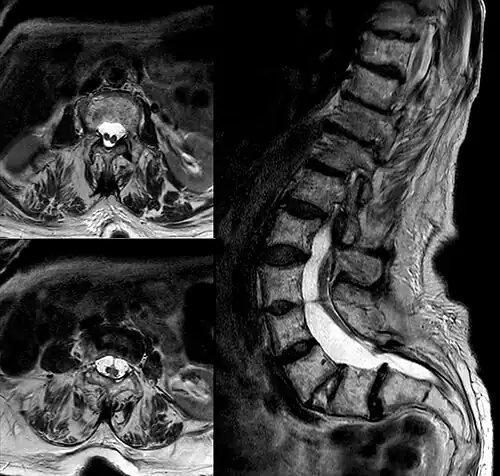

| Diastematomelia in MRI of lumbar spine. | |

In neurology, diastematomyelia (occasionally diastomyelia) is a congenital disorder in which a part of the spinal cord is split, usually at the level of the upper lumbar vertebra in the longitudinal (sagittal) direction. Females are affected much more commonly than males. This condition occurs in the presence of an osseous, cartilaginous or fibrous septum in the central portion of the spinal canal which then produces a complete or incomplete sagittal division of the spinal cord into two hemicords. When the split does not reunite distally to the spur, the condition is referred to as diplomyelia, which is true duplication of the spinal cord.[1]

Diastematomyelia usually occurs between 9th thoracic and 1st sacral levels of the spinal column with most being at the level of the upper lumbar vertebra. Cervical diastematomyelia is a very rare entity. The extent (or length of spinal cord involved) varies from one affected individual to another. In approximately 60% of patients with diastematomyelia, the two hemicords, each covered by an intact layer of pia arachnoid, travel through a single subarachnoid space surrounded by a single dural sac. Each hemicord has its own anterior spinal artery. This form of diastematomyelia is not accompanied by any bony spur or fibrous band and is rarely symptomatic unless hydromyelia or tethering is present. The other 40% of patients have a bony spur or a fibrous band that passes through the two hemicords. In these cases, the dura and arachnoid are split into two separate dural and arachnoidal sacs, each surrounding the corresponding hemicord which are not necessarily symmetric. Each hemicord contains a central canal, one dorsal horn (giving rise to a dorsal nerve root), and one ventral horn (giving rise to a ventral nerve root.) One study showed the bony spur typically situated at the most inferior aspect of the dural cleft. They advised that if the imaging appears to show otherwise, a second spur (present in about 5% of patients with diastematomyelia) is likely to be present. The conus medullaris is situated below the L2 level in more than 75% of these diastematomyelia patients. Thickening of the filum terminale is seen in over half of the cases. While the level of the cleft is variable, it is most commonly found in the lumbar region. The two hemicords usually reunite caudally to the cleft. Occasionally, however, the cleft will extend unusually low and the cord will end with two separate coni medullarae and two fila terminale ("Diplomyelia").

Adult presentation in diastematomyelia is unusual. With modern imaging techniques, various types of spinal dysraphism are being diagnosed in adults with increasing frequency. The commonest location of the lesion is at first to third lumbar vertebrae. Lumbosacral adult diastematomyelia is even rarer. Bony malformations and dysplasias are generally recognized on plain x-rays. MRI scanning is often the first choice of screening and diagnosis. MRI generally give adequate analysis of the spinal cord deformities although it has some limitations in giving detailed bone anatomy. Combined myelographic and post-myelographic CT scan is the most effective diagnostic tool in demonstrating the detailed bone, intradural and extradural pathological anatomy of the affected and adjacent spinal canal levels and of the bony spur.